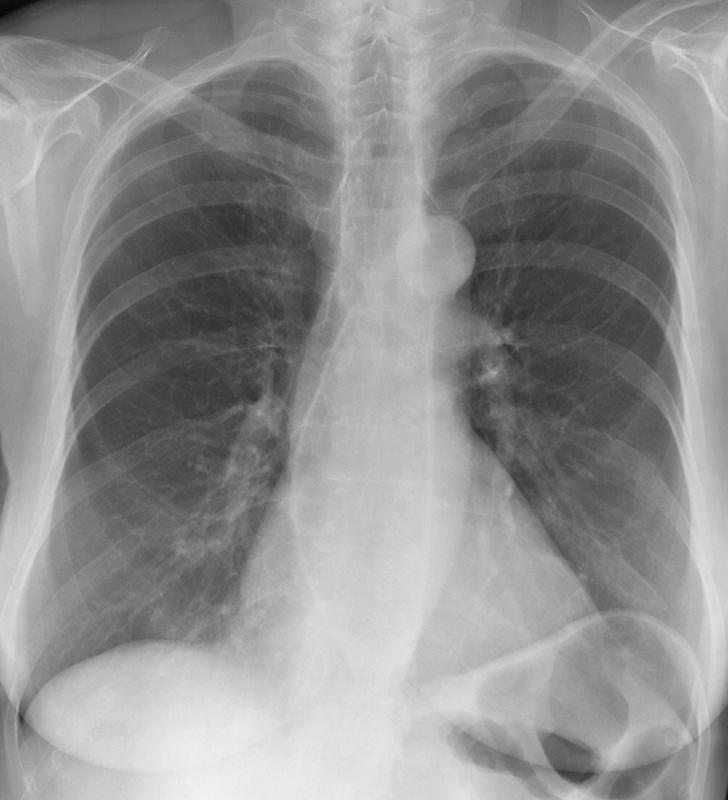

Scleroderma esophagus